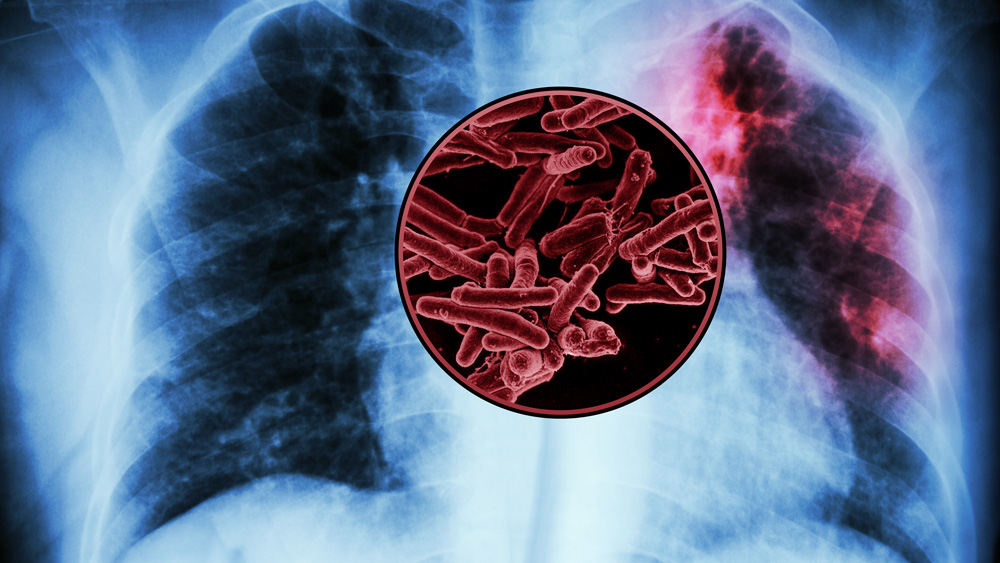

Biological engineers have found several possible targets for a new vaccine against tuberculosis — the world’s deadliest infectious disease, killing more than 1 million people annually. “There’s still a huge TB burden globally,” Bryan Bryson says.